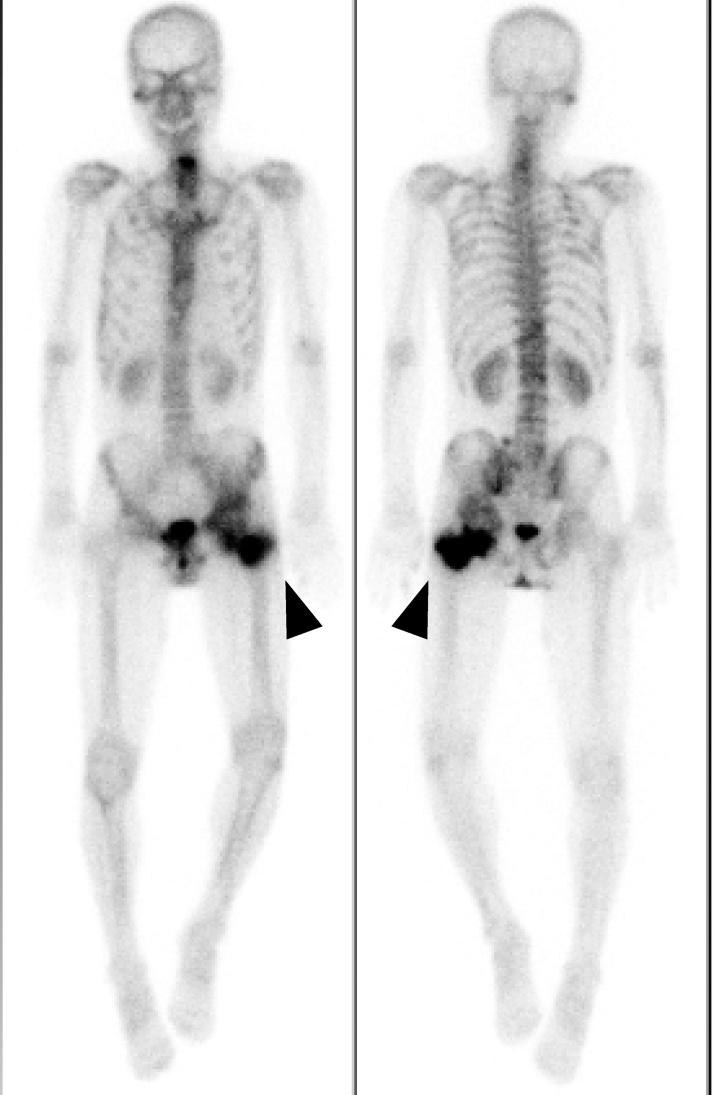

The patient unexpectedly presented to our hospital 6 months after the transfer. He could walk on his own and was completely conscious and alert, but he complained of discomfort in his left hip and difficulty in its motion. Physical examination revealed that his left hip joint was completely ankylosed with a range of motion 45° in flexion, 10° in abduction, and 20° in external rotation. Radiographs and CT revealed HO (Brooker class 4) [3] around the left hip joint (Fig. 2A,B). A bone scan showed intense uptake around the left hip (Fig. 3).

Fig. 3.

On the bone scan image, the arrowheads show increased uptake around the left hip.

Previous studies have indicated that HO resection should be delayed until the HO has matured and the bone scan has normalized to reduce the risk of HO recurrence [6]. Garland and Orwin [11] performed hip HO resection in patients with spinal cord injuries, with a mean time from injury to surgery of 50.6 months. Meiners et al. [12] performed hip HO resection in patients with spinal cord injury at an average of 82.1 months after injury. Conversely, Genet et al. [6] reported that early resection of immature HO did not lead to a higher rate of recurrence. Wu et al. [10] reported no significant difference in the HO recurrence rate between early and delayed HO resection. They also reported that it was easier to identify the border between HO and normal cortex during the operation if the time interval before HO resection was short. They recommended early HO resection because it enables an easier operation, an earlier start of rehabilitation, and prevention of complications such as intraoperative fracture of the femoral neck, wound infection, and sciatic nerve injury [6,11]. Melamed et al. [13] suggested that increased uptake on bone scans was not a contraindication to surgical excision of HO, provided the neurologic status is stabilized. We performed HO resection 9.5 months after the initial operation despite the fact that the uptake on the bone scan was still intense. Cobb et al. [14] performed HO resection at a mean of 13 months after total hip arthroplasty. We considered that waiting for several years would lead to more disability in our patient, and 9.5 months after the initial operation was not a contraindication for HO resection surgery.